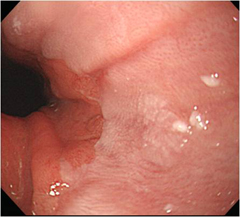

À§¾ÏÀÇ ³»½Ã°æ »çÁø

¾Ç¼ºÁ¾¾çÀº?

À§¾Ï, ½Äµµ¾Ï°ú °°Àº ÁúȯÀ¸·Î ´Ù¸¥ º´°ú´Â Áõ»ó¸¸À¸·Î´Â ±¸ºÐÀÌ ¾ÈµÇ¸ç, üÁß°¨¼Ò, Àü½Å ¼è¾à°¨, Èæ»öº¯ µîÀÇ Áõ»óÀ» µ¿¹ÝÇÑ´Ù.